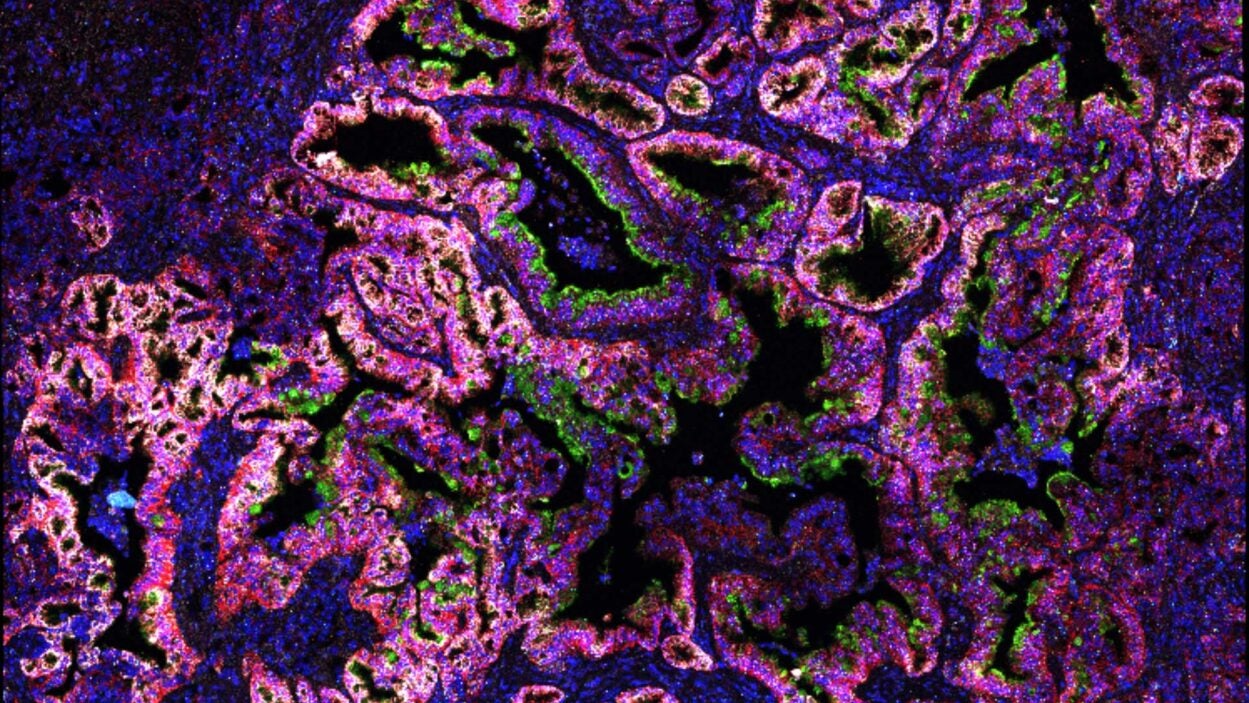

Feature

An angry peacock is no joke. Like the colorful bird and its tall tail feathers, cancer biology can make for some eye-catching images. Read the story »

That’s not the Starship Enterprise burning up in space. It’s an up-close look at precancerous pancreatic lesions and the mucus they produce. Read the story »

Mucus is not just snot. CSHL scientists have discovered some pancreatic cancer cells depend on it. The finding may open a new therapeutic avenue. Read the story »